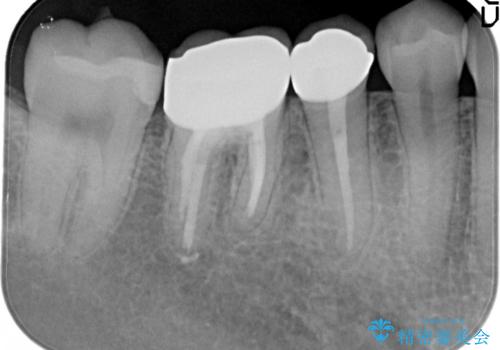

【メタルフリー】銀歯を白くしたい。オールセラミッククラウン。

- 銀歯を白くしたいと希望され来院されました。

すぐにでも白くしたいとのことで、2回目の来院で銀歯を白い仮歯に変更し喜んでいただきました。

根管治療は林先生に依頼しております。

- 70万円費用は治療当時の料金となります

ただ単純に白くするでけではなく拡大鏡を使用し、丁寧な処置を行なっております。